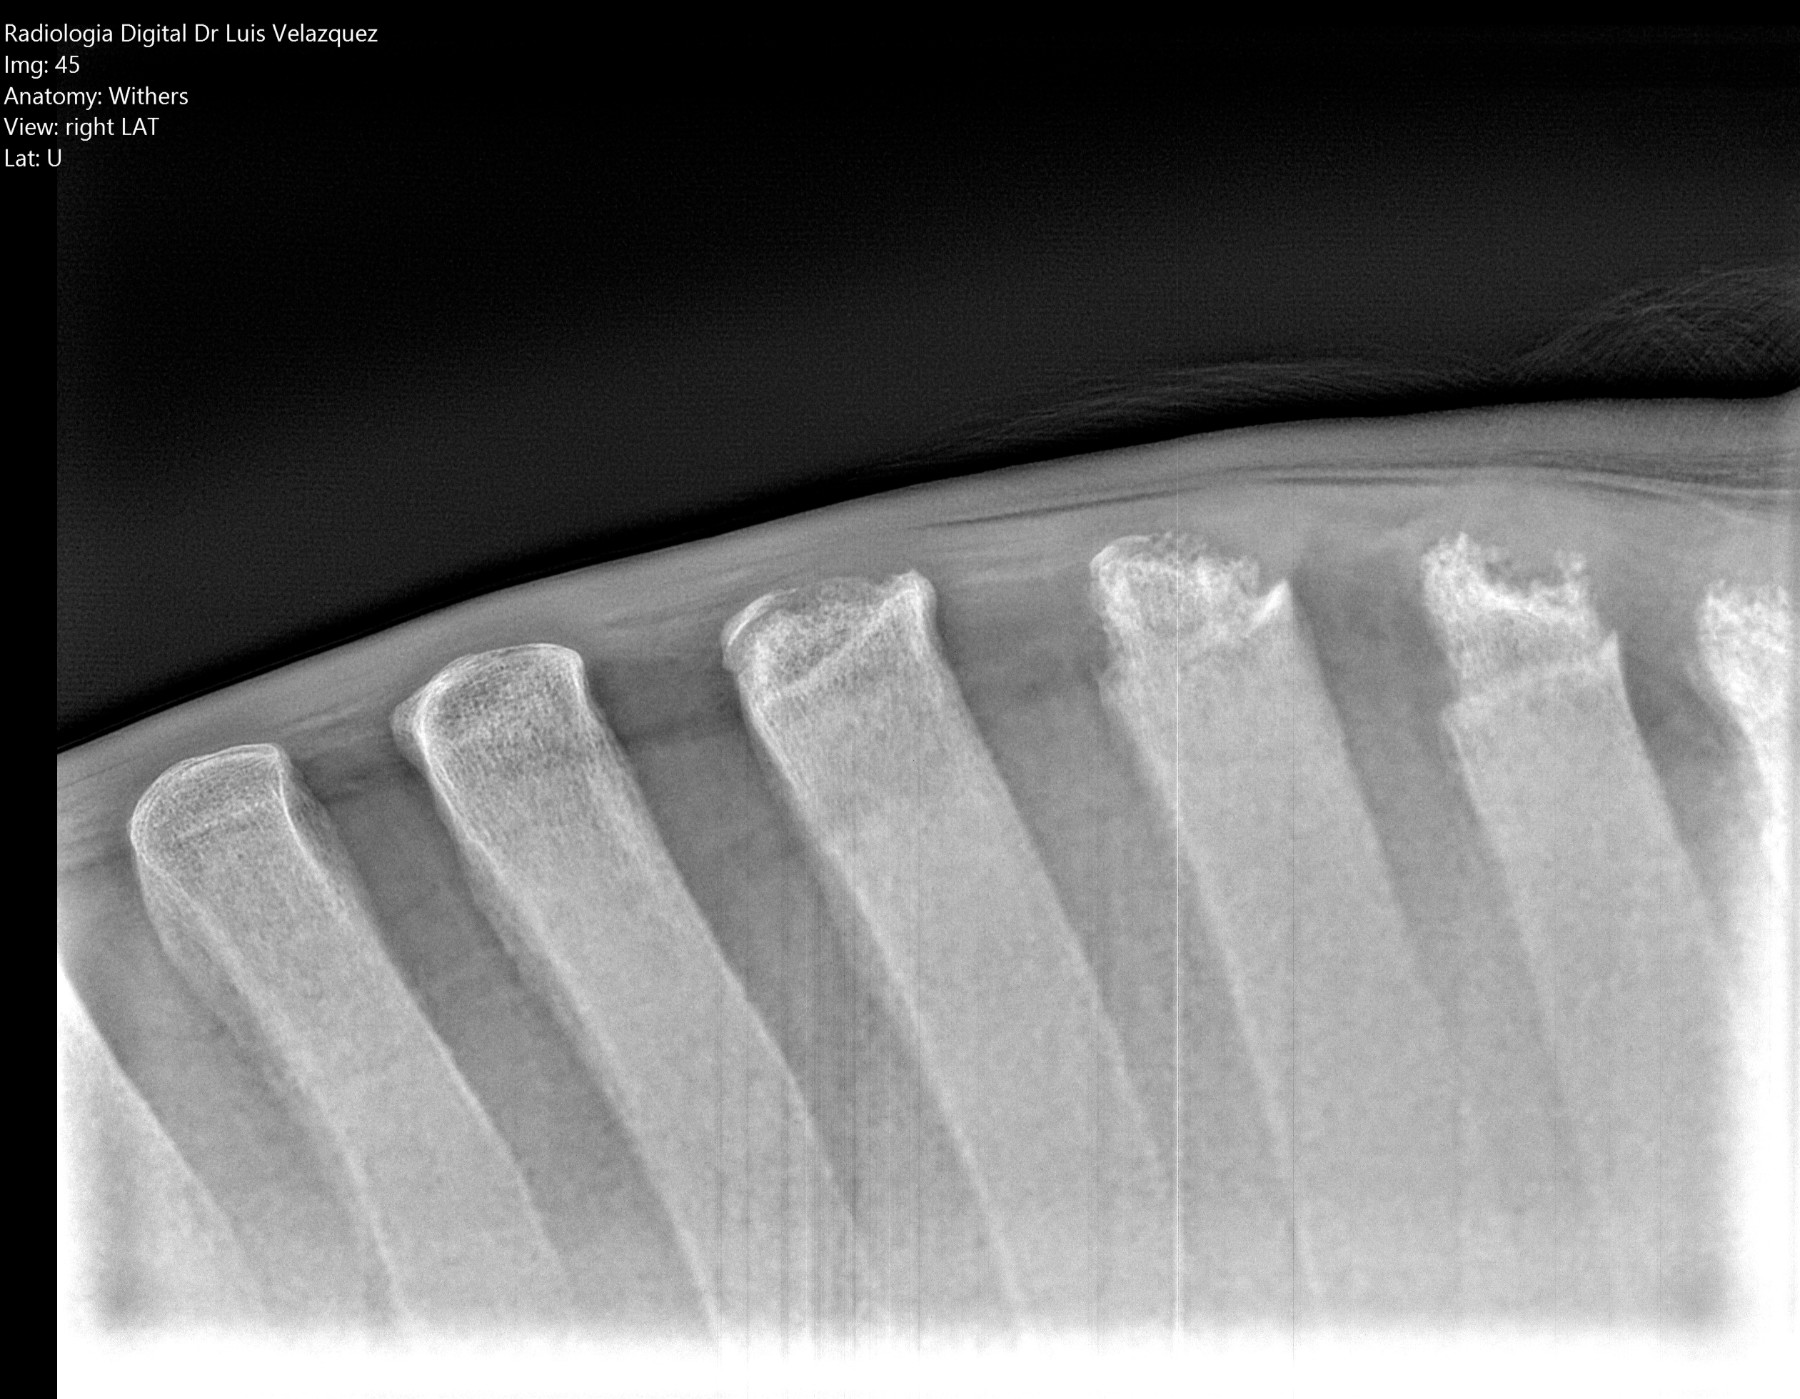

Cambios Térmicos en las Extremidades de Caballos,

Asociados a Golpes y su Evaluación por Termografía.

Los caballos de salto, en competencia, pueden derribar obstáculos y lastimarse. Si se golpean, no siempre claudican. Considerando al calor como un signo de inflamación, se evaluaron los cambios térmicos de 6 áreas de las extremidades torácicas y pelvianas de 23 caballos de salto en nivel de competencia de 1.05 a 1.60 m de altura, por medio de termografía durante 4 días de competencia (N=2208 áreas).